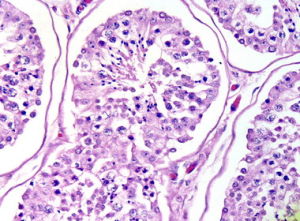

支原體只能粘附在呼吸道或泌尿生殖道的上皮細胞表面的受體上,而不進入組織和血

泌尿生殖道在動物實驗發現,小鼠腹腔巨噬細胞可以殺滅支原體,而中性粒細胞的作用不大。在體外,IgG1和IgG2抗體有調理作用。可加強巨噬細胞對支原體的殺傷作用。